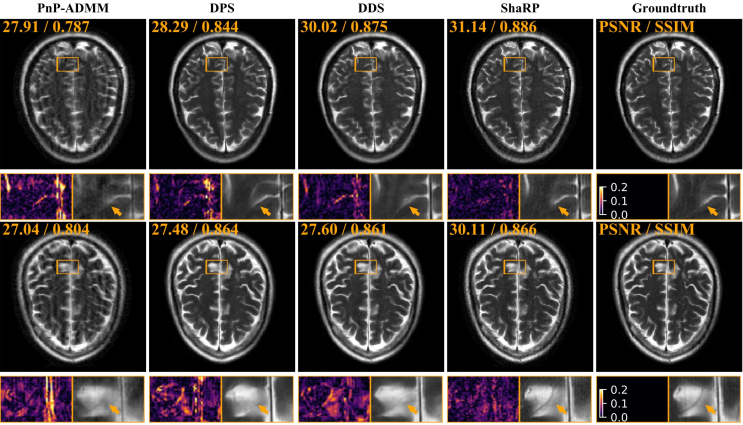

Results with supervised MMSE Restoration operator. Figure 2 illustrates the convergence behavior of ShaRP on the test set with an acceleration factor of R=6𝑅6R=6 and additional noise σ=0.01𝜎0.01\sigma=0.01. Table 1 provides a quantitative comparison of reconstruction performance across different acceleration factors and noise levels using a uniform sub-sampling mask. In all configurations, ShaRP consistently outperforms the baseline methods. The use of a set of restoration operators clearly enhances ShaRP’s performance, highlighting the effectiveness of employing multiple operators to maximize the regularization information provided by the restoration model. Figure 3 presents visual reconstructions for two test scenarios, where ShaRP accurately recovers fine brain details, particularly in the zoomed-in regions, while baseline methods tend to oversmooth or introduce artifacts. These results highlight ShaRP’s superior ability to manage structured artifacts and preserve fine details, outperforming both denoiser-based and diffusion model-based methods.

Refer to caption

Figure 3: Visual comparison of ShaRP with baseline methods on CS-MRI. The top row shows results for a 4×4\times random mask with noise σ=0.005𝜎0.005\sigma=0.005, and the bottom row for a 6×6\times random mask with noise σ=0.015𝜎0.015\sigma=0.015. PSNR and SSIM values are in the top-left corner of each image. Error maps and zoomed-in areas highlight differences. Notably, ShaRP with stochastic priors outperforms state-of-the-art methods using denoiser and diffusion model priors.